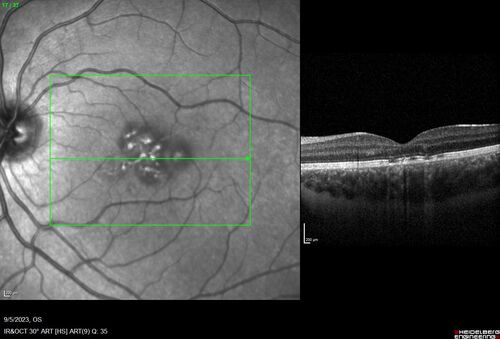

Laser pointer maculopathy

11 year old male When school started the patient noticed that he was having trouble reading and seeing out of both eyes. There are no retinal diseases in the family.

VA OD: sc20/25

VA OS: sc20/40

TP: OD:19 OS:18